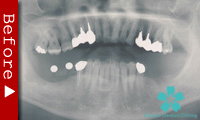

歯が全くない場合

下顎の歯が1本もない場合の修復には、インプラントが良く利用されます。

インプラントのヘッド部をバー状の維持装置で連結し、その上に取り外し式の入れ歯をしっかりと固定することができます。